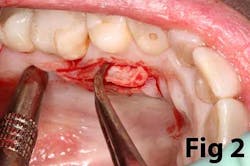

Gingival recession is the result of loss of alveolar bone and tissue, specifically AG. A high number of recession cases result in less than the minimum required amount of AG. (Fig. 4) Similarly, following tooth extraction or long-standing edentulism (without bone preservation), loss of alveolar dimension is accompanied with diminishing AG. (Fig. 5)Note: specific cases may also be attributed to gingival biotype and genetic predisposition.